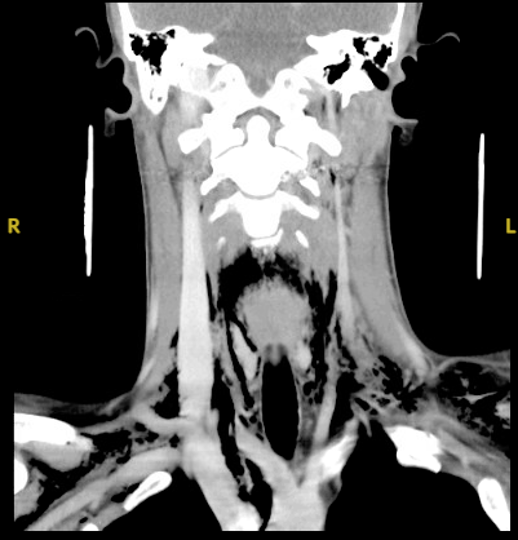

Diagnostic testing. The patient’s white cell count was 12.04 (normal range, 3.50-10.80) and his creatinine was 2.70 (normal range, 0.7-1.2). Although no alcohol was detected in his blood sample, a drug screening was positive for amphetamines and cannabinoids. His respiratory viral panel was negative, and his rapid step was positive. The oral ulcer was cultured as well. Due to his trouble swallowing, a chest x-ray was obtained (Figure 1), which showed pneumomediastinum. The patient’s chest and neck computed tomography (CT) showed moderate pneumomediastinum (Figure 2) and extensive subcutaneous emphysema within the base of the neck (Figure 3).

Fig. 3. The patient’s soft tissue neck CT with contrast is shown.